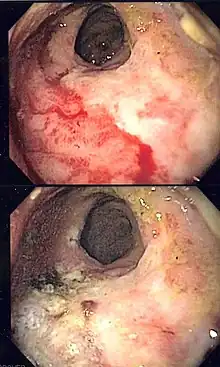

Endoscopic image of radiation associated vascular ectasias (RAVE) before and after therapy with argon plasma coagulation.

Endoscopy is the mainstay of diagnosis for radiation damage to the rectum, with either colonoscopy or flexible sigmoidoscopy. RAVE is usually recognized by the macroscopic appearances on endoscopy characterized by vascular ectasias.[8] Mucosal biopsy may aid in ruling out alternate causes of proctitis, but is not routinely necessary and may increase the risk of fistulae development.[6] Telangiectasias are characteristic and prone to bleeding.[3] Additional endoscopic findings may include pallor (pale appearance), edema, and friability of the mucosa.